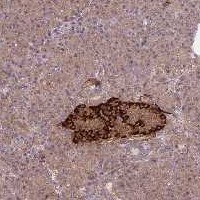

Immunohistochemical staining of human pancreas shows strong cytoplasmic positivity in islets of Langerhans.